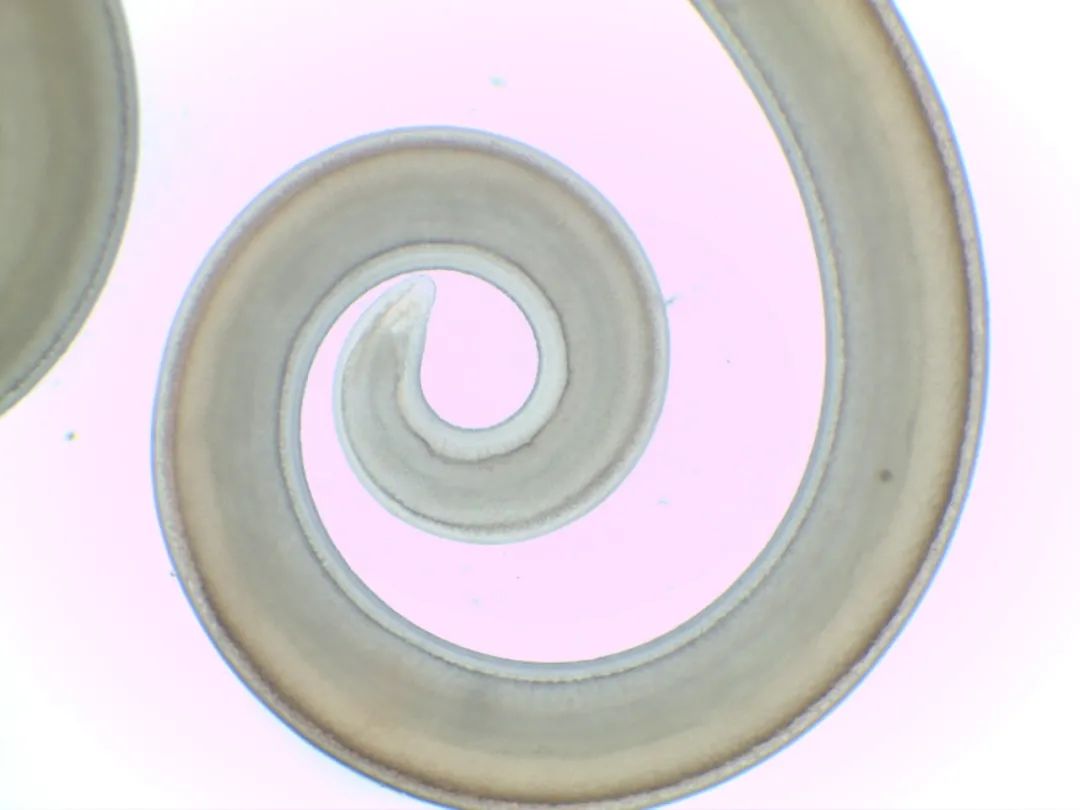

顯微鏡下的異尖線蟲

異尖線蟲是寄生于海洋哺乳動物的線蟲,其幼蟲主要寄生于海棲魚類,人的感染主要是食入了含異尖線蟲的三期幼蟲的海魚和海產軟體動物而引起。

海魚體內分離出的異尖線蟲